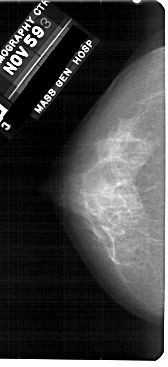

A_1907_1.LEFT_MLO

LEFT_MLO LINES 5206 PIXELS_PER_LINE 2716 BITS_PER_PIXEL 12 RESOLUTION 43.5 NON_OVERLAY